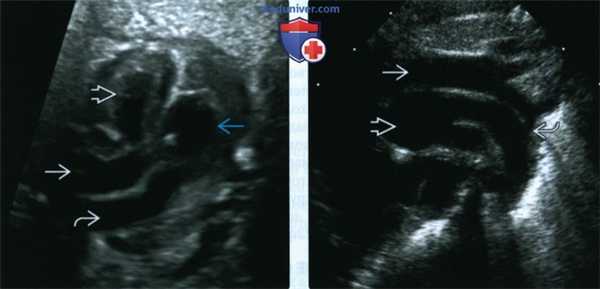

(Слева) Простая транспозиция без ДМЖП. Аорта отходит от ПЖ, а легочная артерия - от ЛЖ. Крупные сосуды идут параллельно друг другу и не пересекаются, как должно быть в норме.

(Справа) Четырехкамерный срез у плода с транспозицией магистральных артерий и ДМЖП. Нарушения не определяются. ПЖ расположен спереди, а ЛЖ - сзади. Смещение плоскости четырехкамерного среза по направлению к магистральным сосудам иногда позволяет диагностировать ВПС. (Слева) После того как датчик был смещен кпереди, начал определяться крупный ДМЖП. Магистральный сосуд, расположенный выше дефекта, рано дает ветви (характерно для легочной артерии); данный признак является подтверждением диагноза транспозиции магистральных артерий.

(Справа) То же изображение в режиме ЦДК. Кровоток из ПЖ и ЛЖ попадает в легочную артерию. Необходимо обращать внимание на размер аорты, и если он уступает размерам легочной артерии, можно заподозрить коарктацию аорты.

(Слева) УЗИ. Определяются ветвление легочной артерии отходящей от расположенного сзади желудочка (ЛЖ), и аорта, отходящая от желудочка, расположенного спереди (ПЖ).

(Справа) УЗИ. Аорта проходит спереди от легочной артерии, размеры сосудов значительно отличаются. Если данная находка обнаружена у пациента с транспозицией магистральных артерий и ДМЖП, необходимо исключить обструкцию дуги аорты. У данного пациента диагностированы коарктация аорты, а также гипоплазии поперечной части дуги и перешейка аорты.